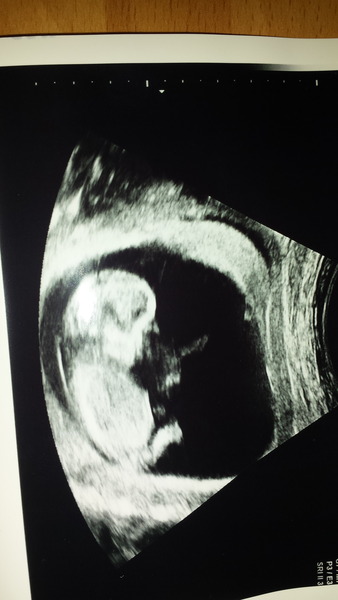

I didnt want to join before as when i lost my dd back in august, leaving the mn antenatal group was one of the hardest things i had to do. But have just had a positive 12 week scan (which is where things started to go wrong last time) so have finally plucked up the courage to say hello!

All being well this will be my first living child so im anxious but so far so good! I shall read back through the thread now and try and catch up with who everyone is - is there a stats sheet?

According to scan im 12+4 today and incredibly glad to be nearly clear of first tri!

Congrats to the new joiners, and I love the scan pic, primary!